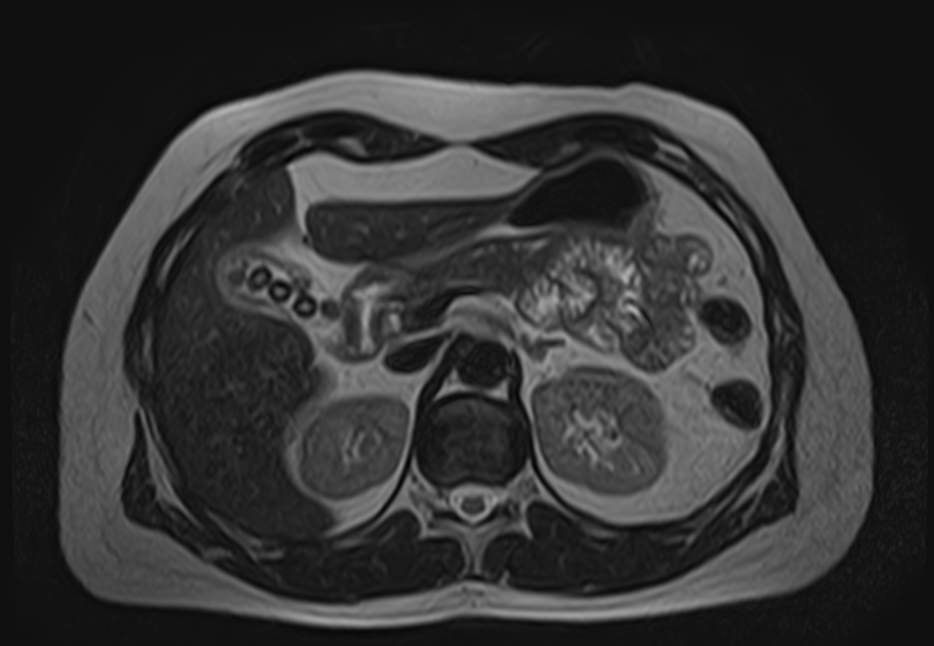

Магнитно-резонансная холангиография – это неинвазивный и безопасный метод исследования, который используется для визуализации желчевыводящих путей, включая внутри- и внепеченочные желчные протоки, панкреатический (Вирсунгов) проток и общий желчный проток (холедох). МРТ позволяет оценить анатомические особенности билиарной системы и определить патологию расположенных рядом структур.

Патология билиарной системы проявляется в виде непроходимости желчных протоков и затруднением оттока желчи. Нарушение отделения желчи может быть вызвано наличием камней, развитием объемного образования внутри протока или сдавлением протока опухолью извне.

С помощью магнитно-резонансной холангиографии можно выявить следующие патологии:

- Острое или хроническое воспаление панкреатобилиарной системы;

- Закупорка протоков конкрементами;

- Доброкачественные и злокачественные опухоли внутри просвета протоков или новообразования, исходящие из окружающих тканей;

- Рубцовые деформации, спайки, стриктуры желчевыводящих путей.

- Аномалии развития желчевыводящей системы.